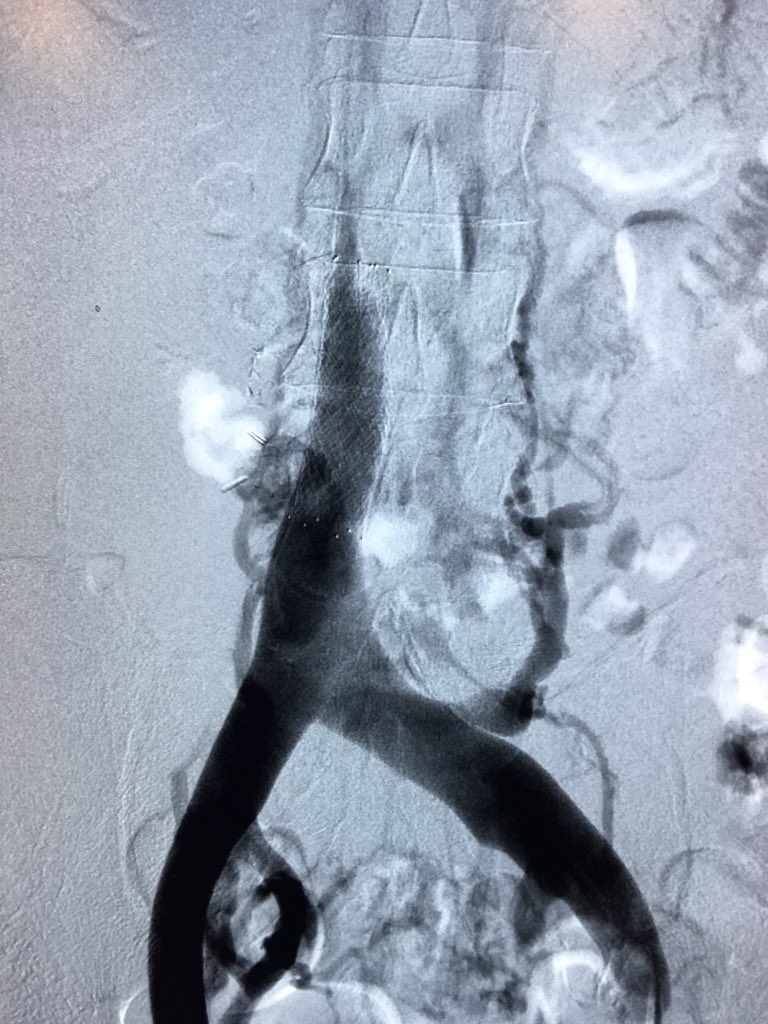

Part1- There are bleeding duodenal ulcers, and then there's this! #irad @SIRRFS @allen_herr @Cstark84 #gobbleonthis